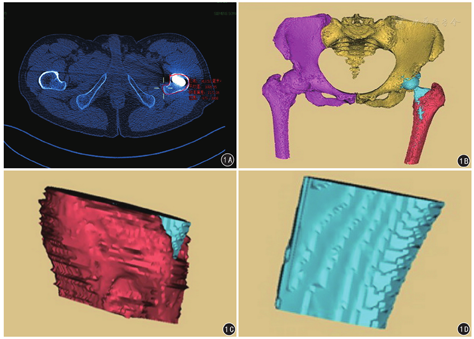

(1)一般资料:比较两组患者性别、年龄及髓腔闪烁指数(canal flare index, CFI)等。(2)治疗效果:对患者术后第2日髋部疼痛改善情况进行VAS评估;术后12周使用Harris髋关节评分(harris hip score, HHS)标准评价患者髋部的整体功能,具体从疼痛、功能、髋关节活动和肢体畸形四个方面来评估,90~100分为优、80~89分较好,70~79分为尚可,<70分为差。(3)股骨假体位置及稳定性评估:参考Mulliken标准,术后即刻采用X线测量评估股骨假体置换后股骨柄的初始位置,以股骨柄居中或内外翻角度≤3°,同时股骨柄压配率于X线正位片达80%、侧位片达70%为股骨柄初始稳定性优良,未达此标准的为差。(4)双下肢绝对长度差:在手术前后双髋X线正位片上,分别测量双侧小转子基底部到坐骨结节连线的高度,记录两侧差值。(5)两组假体骨量保留参数比较:基于CT三维重建影像,于股骨小转子最宽部层面,测量股骨外层皮质、假体外层平面的面积,两者差值即为小转子最宽部骨量保留面积;应用Mimics 17.0软件重建并测量大转子最宽部至小转子最宽部容量体积,减去对应部位的假体体积,即为大小转子间骨量保留体积。见图1。(6)术中及术后早期并发症:股骨近端医源性骨折、大腿远端疼痛等。

Tri-Lock BPS具有如下特点[6]:(1)采用股骨柄扁平、双面锥化设计,更加匹配股骨髓腔的生理解剖形态,即近端膨大、远端狭窄,能在股骨颈及近端干骺端区域获得良好的填充压配,提供了优良的初始稳定性[7]。(2)缩小股骨柄远端长度和宽度,减少或不扩大远端峡部髓腔,保留远端峡部骨量。(3)较之传统的45°截骨线,50°截骨线可有效保留股骨距部骨量。Hammer[8]指出,股骨距为人体负重的重要构成部分,它作为真正的股骨颈起到承上启下重要作用,股骨距部骨量的增加减少了操作过程中股骨近端医源性骨折的发生。(4)削肩设计,锉磨过程中远离了大转子区域,保留更多的股骨近端大转子部骨量,并避免了磨锉过程中对臀中肌的大转子止点部潜在损伤。(5)股骨柄的远端采取应力分散的设计,减少了因应力集中于股骨柄远端而导致近端大粗隆部失应力的骨量流失[9],也减少了术后大腿远端疼痛的发生率[6]。针对上述特点,本研究中采用股骨小转子最宽部区域骨量的面积,并重点数字重建股骨大小转子最宽部间区域,以此来观察具体骨量保留情况,将抽象的骨量保留概念数字化,证实了观察组较对照组能在此区域内有效保留骨量,可为后期翻修预留切实可靠的骨量空间。